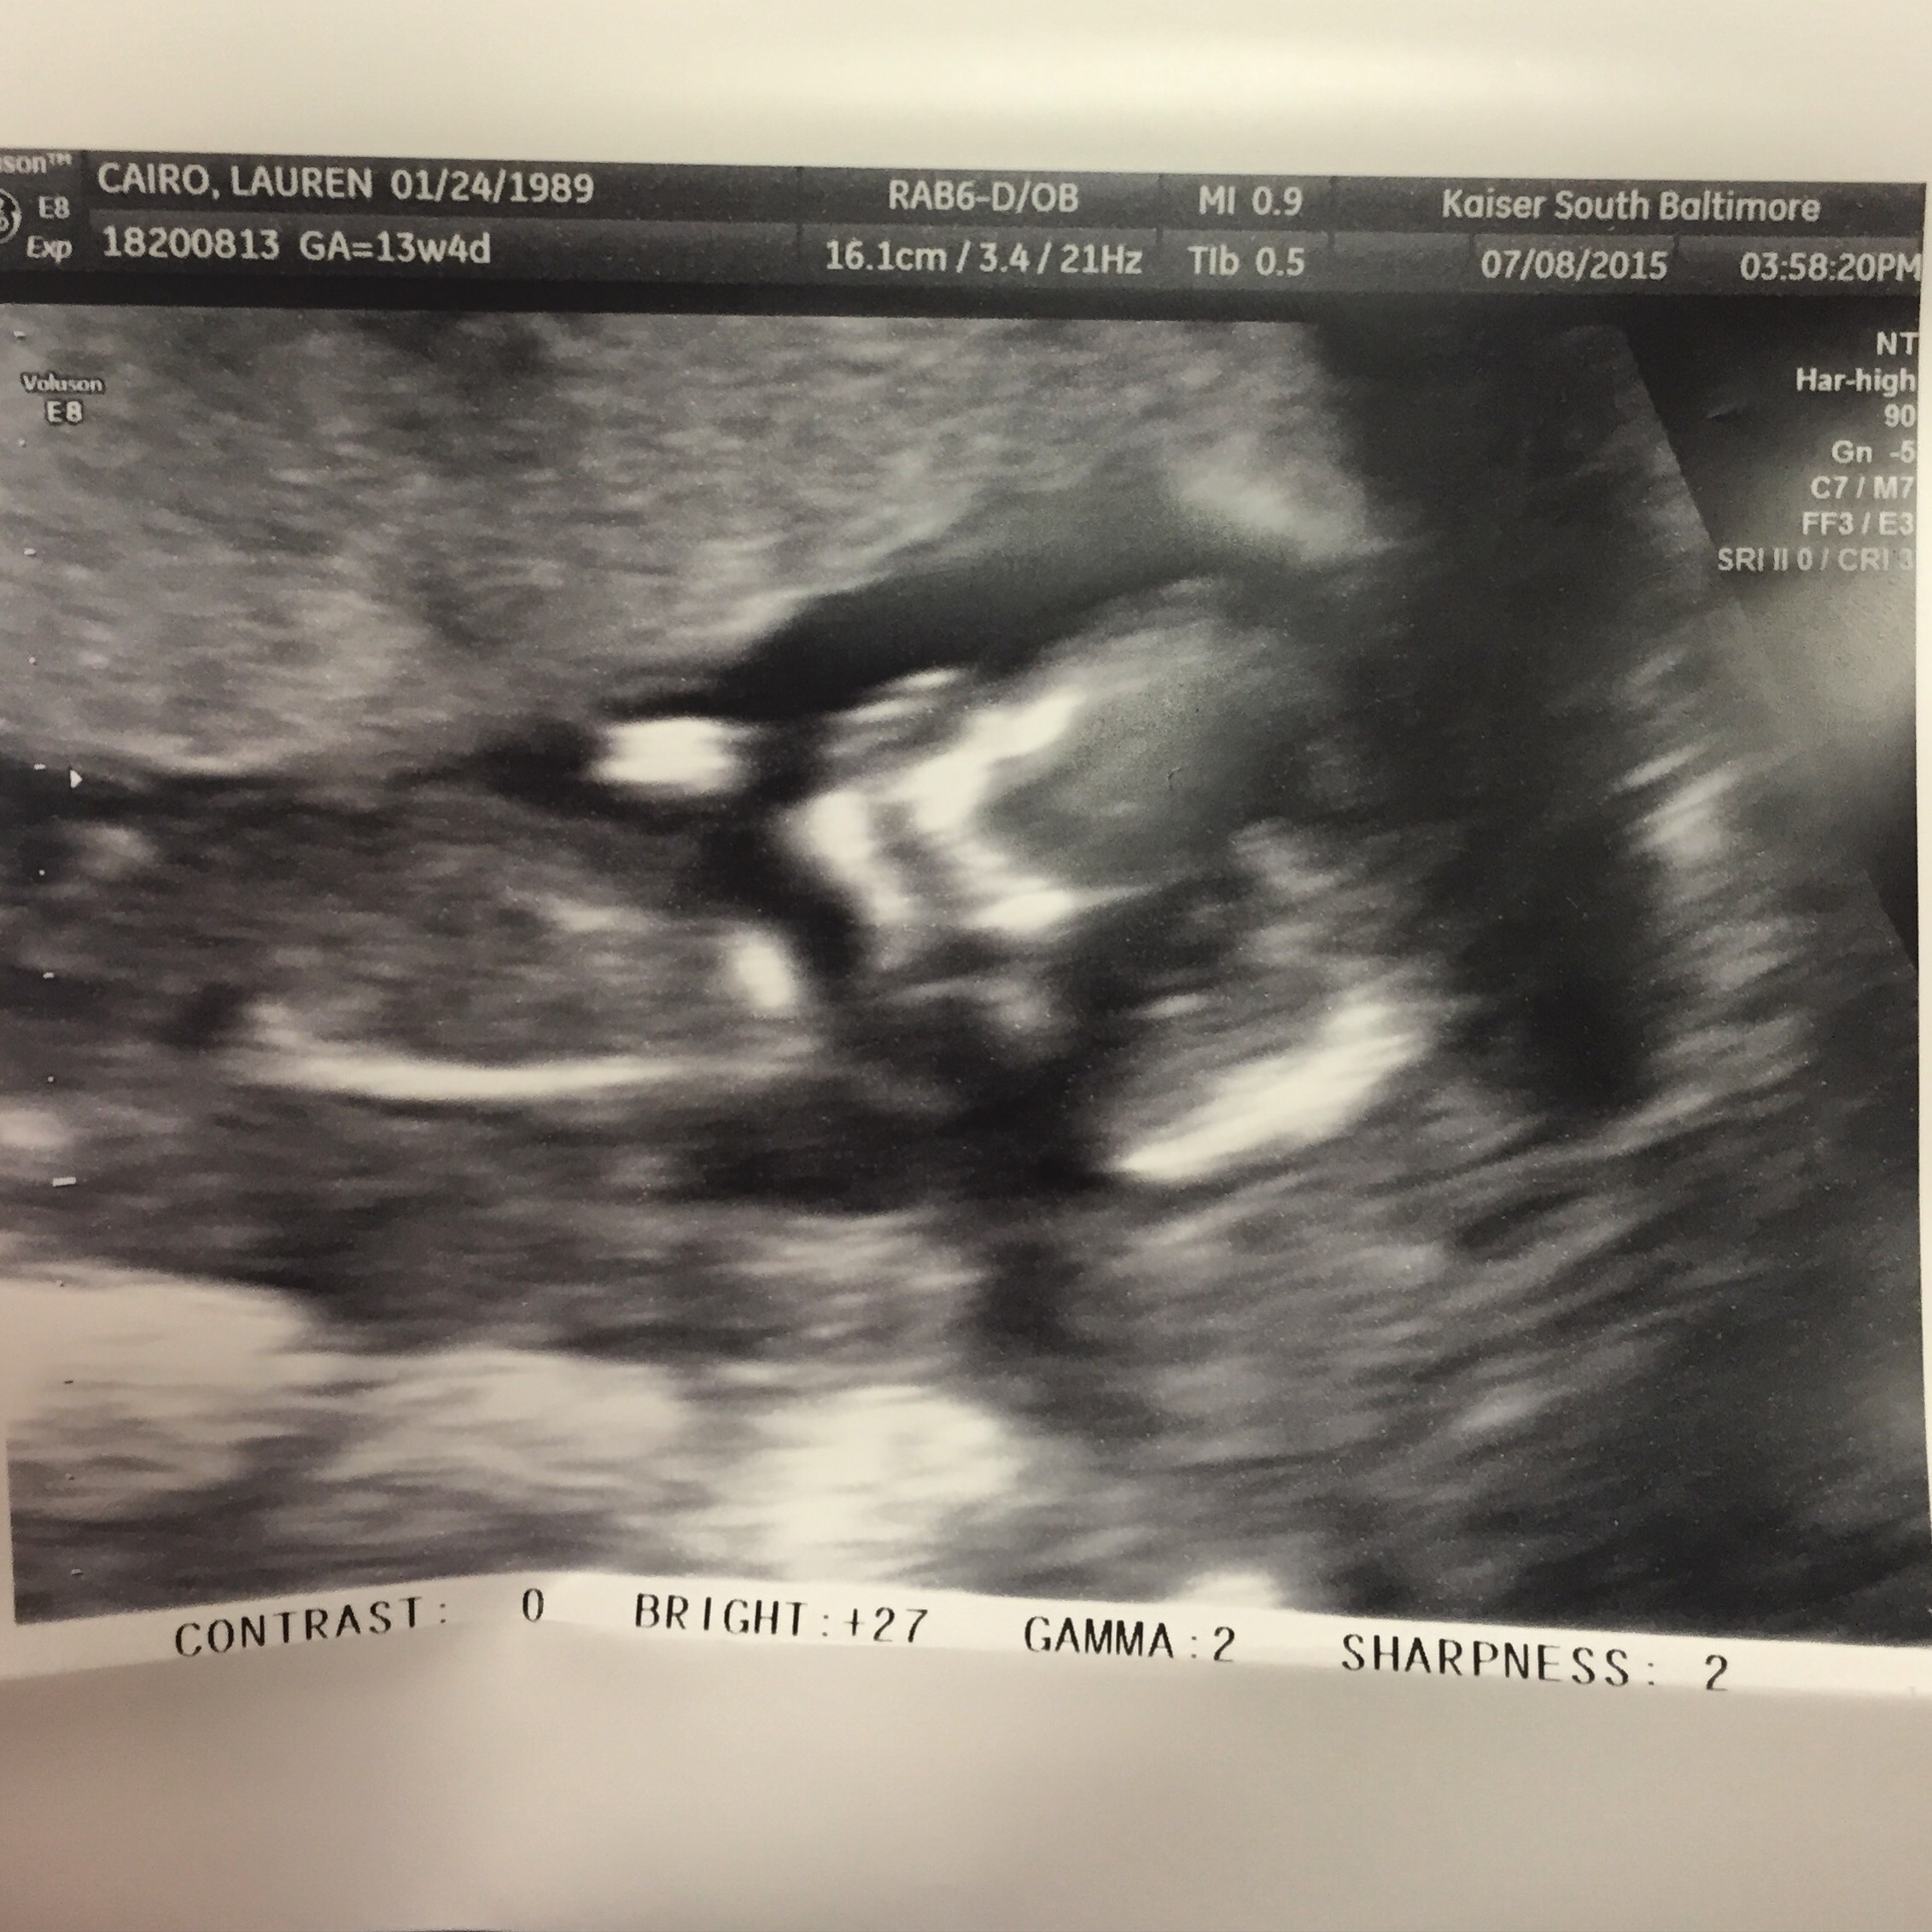

Here are my twins from my 13 week ultrasound. Both have strong heartbeats! One measuring at 13 weeks 4 days and the other 13 weeks 6 days. Tech made a guess and thinks they're boys!!